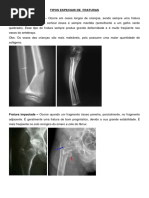

 GRAU I: exposição menos que 1cm, tem fratura com exposição até 1cm.